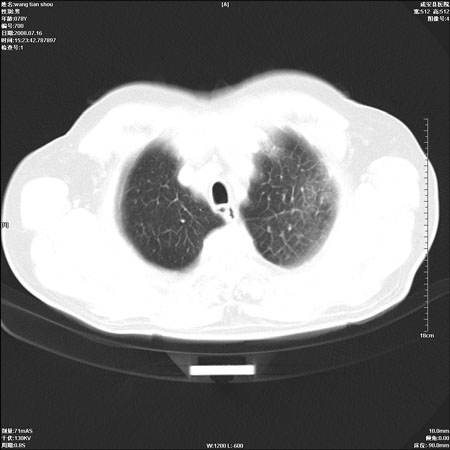

以下是引用qingjing在2008-7-16 19:55:00的发言:[br]1、左上肺不张并堵塞性炎症,建议支气管镜详查;[br]2、左侧胸腔少量积液。

以下是引用wzr在2008-7-16 20:26:00的发言:[br]左肺肺不张伴阻塞性肺炎!另:左侧胸腔少量积液。建议纤支镜检查!